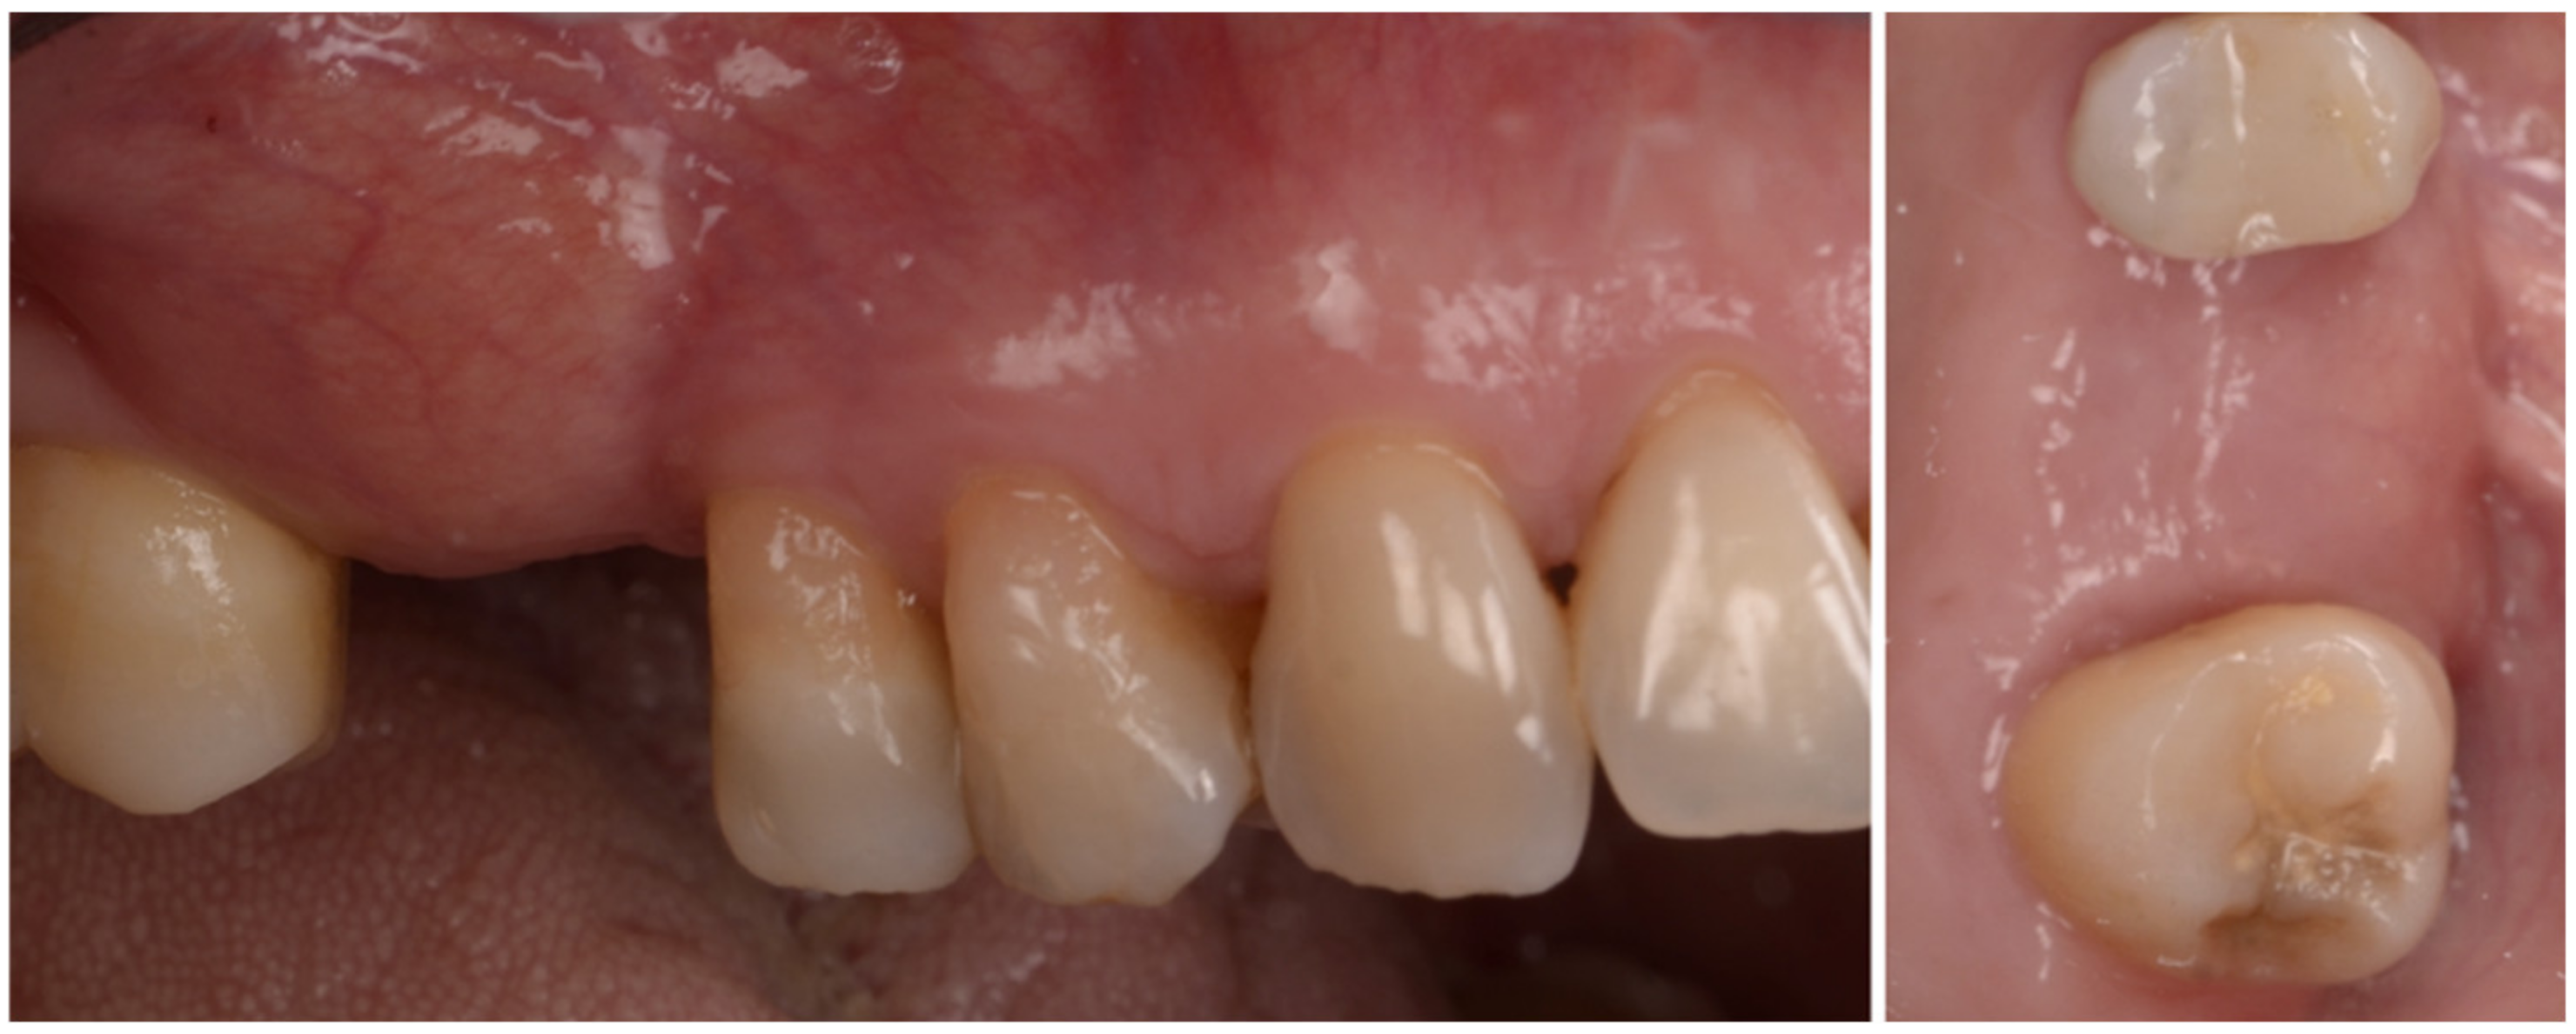

Six months after surgery the area looked really different from the clinical and radiographic point of view; soft tissue sits near the CEJ of the teeth and a buccal bulk is restored. (Figure 8 and Figure 9).

Figure 8.

At 6 months both the hard and soft tissue augmentation is evident.

A common finding when treating patients with collagenated devices is a good amount of keratinized gingiva after healing. At the time of implant placement the quality of the bone and primary stability of the fixture was excellent; an ISQ of 79 suggested the placement of a healing abutment and the suturing of the buccal flap to the buccal aspect of the healing abutment in order to restore the correct amount of keratinized gingiva and vestibule (Figure 10).

Figure 10.

Fixture placed in the regenerated ridge, healing abutment in place and buccal repositioning of the keratinized gingiva.

Three weeks later a temporary crown in PMMA was connected to the implant to condition the soft tissue and recreate interdental papilla, and after a couple of months the final restoration, a PFM crown, was connected to the implant (Figure 11).

Figure 11.

Baseline, after conditioning and final restoration.

The case has been followed for over three years and the stability of the soft and hard tissue are proof of the GTR effect of GBR. In this case, all parameters were restored in a still very young patient (Figure 12). The important aspect of the GTR effect is that teeth otherwise compromised at a young age are back in function with the support of both soft and hard tissue and all of this with only two surgical procedures. The presence of interdental-implant papilla is important to prevent food impaction and make the maintenance similar to that of the natural dentition. PPD at the time of recall were 2 mm to the distal of 15 and 2 mm to the mesial of 17; compared to the baseline, the gain of attachment was 4 mm for 15 and 5 mm for 17.

Figure 12.

Baseline and clinical and radiographic result 36 months after loading.